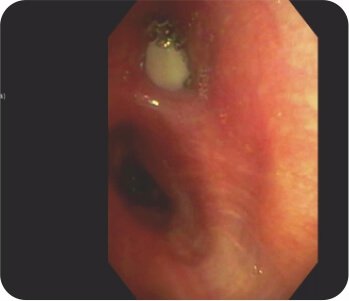

সিটি বুক বাম উপরের লোবে গহ্বরের ইঙ্গিত দেয়। এফওবি বাম উপরের লোব ব্রঙ্কাস থেকে পুস নির্গত হওয়ার পরামর্শ দিয়েছিল এবং বাম উপরের লোব ব্রঙ্কাসে একটি জমাট ভরের সাথে অনুগত। পরবর্তী ব্রঙ্কোঅ্যালভিওলার ল্যাভেজ প্রধানত নিউট্রোফিলিক ছিল। পাইজেনিক, ছত্রাক, যক্ষ্মা এবং নোকার্ডিয়ার জন্য দাগ এবং সংস্কৃতি নেতিবাচক ছিল। সাইটোলজি ম্যালিগন্যান্সির জন্য নেতিবাচক ছিল। ইনভেসিভ মিউকোরমাইকোসিসের একটি নির্ণয় করা হয়েছিল।

ব্রঙ্কোস্কোপি – বাম উপরের লোব ব্রঙ্কাস থেকে পুঁজ বের হওয়া

ব্রঙ্কোস্কোপি - বাম উপরের লোব ব্রঙ্কাসে ভর/জমাট বাঁধা